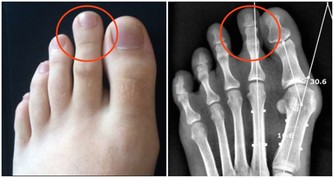

1、長期處在壓力中,健康最容易亮起紅燈。(健康隱患:慢性疲勞綜合徵)

2、對流行性感冒病毒防衛能力最差。(健康隱患:流行性感冒)

3、消化道容易受到細菌感染。(健康隱患:腹瀉、痢疾)